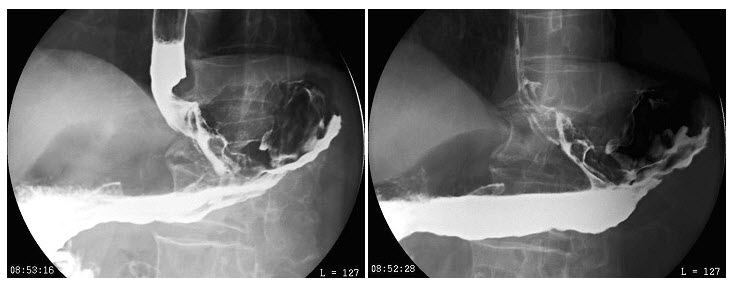

- 单项选择题男,75岁,吞咽困难3月,伴胸痛,结合图像,最可能的诊断为()

A、贲门癌

B、胃底癌

C、食管下段癌

D、贲门癌侵及食管、胃底

E、食管胃底静脉曲张

- D